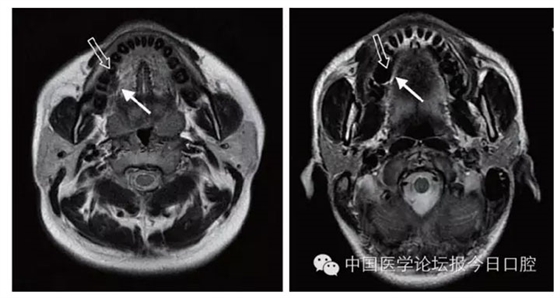

文獻研究中常使用的金屬包括鎳鉻合金、鈷鉻合金、低鈦合金、純鈦、金合金、金鈀合金、銀鈀合金等成分如表所示。大量研究得出近乎一致性的結(jié)論。金合金、金鈀合金、銀鈀合金對MRI影響甚微,與全瓷材料、丙烯酸樹脂極為相似,表現(xiàn)為修復(fù)體影像邊緣光滑、無變形、無偽影;純鈦金屬對MRI影響較小,接近于全瓷材料;但有的研究卻發(fā)現(xiàn)純鈦在核磁共振場中也產(chǎn)生偽影,但偽影涉及的掃描層數(shù)較少;低鈦合金(鈦合金)對MRI影響較大,介于純鈦和鎳鉻合金之間,中度偽影;鎳鉻合金、鈷鉻合金對MRI影響很大,鈷鉻合金更甚;表現(xiàn)為重度偽影、圖像扭曲變形(圖1、圖2)。不難看出,對MRI影響,全瓷材料、樹脂材料<金合金等貴金屬<純鈦<低鈦合金<鎳鉻合金<鈷鉻合金。有研究發(fā)現(xiàn)鈷鉻合金橋偽影大小與修復(fù)體長軸一致,影響范圍為固定橋近遠中徑2倍,頰舌徑的4倍;相同外形金屬修復(fù)體厚度增加,偽影增加。單個金屬樁核偽影可波及到上頜竇、牙槽骨、舌體、舌下腺等組織器官,但對眼底、眼內(nèi)容物、腦組織和頸椎成像基本無影響。

圖2 4種金屬冠在犬MRI檢查中的影響,圖片引自《實用口腔醫(yī)學(xué)雜志》2014第30期《4種金屬冠對磁共振成像影響的對比研究》一文,作者高嵐等